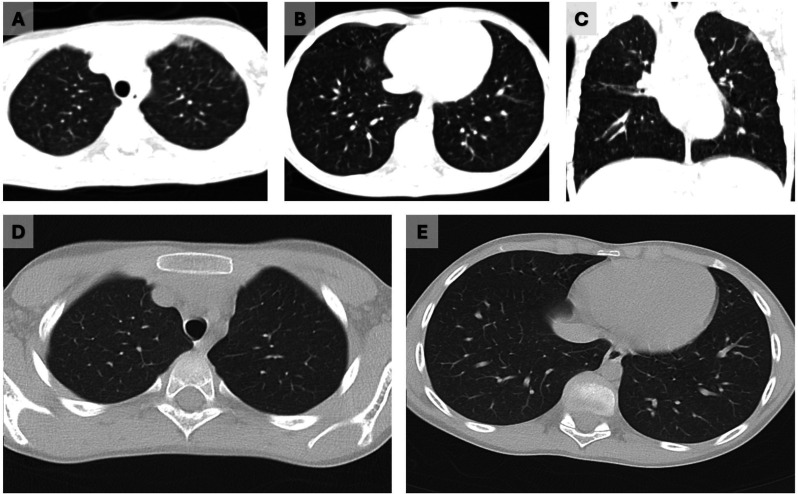

Abstract Image